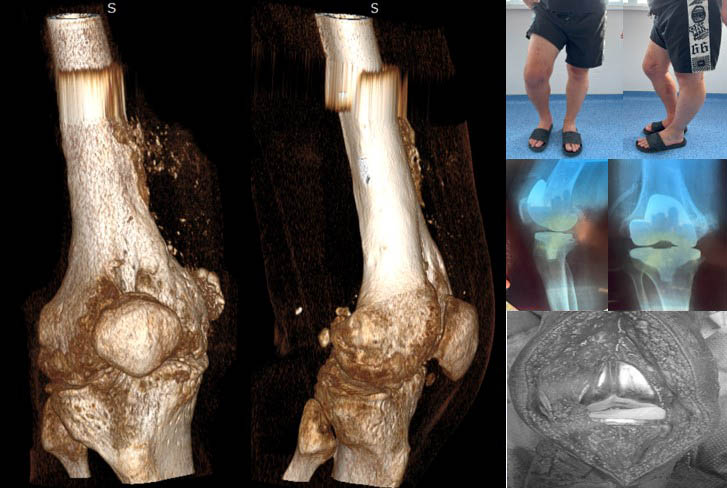

Пацієнт С,30 років. Військовослужбовець, 01.11.2022 отримав мінно-вибухову травму, вогнепальне уламкове наскрізне поранення нижньої третини правого стегна з відкритим переломом медіального виростка з повним пересіченням підколінної артерії, підколінної вени та підколінного нерва.

Пацієнт Д.,30 років. Військовослужбовець, 15.08.2023 отримав мінно-вибухову травму, вогнепальне уламкове наскрізне поранення нижньої третини правої гомілки.

В лабораторії Біомедичної інженерії ІТО НАМН України виконано проектування індивідуального аугменту.

Етапи проектування індивідуальних аугументів для ревізійного ендопротезування колінного суглоба

Паціент М., Міно-вибухове поранення кісток колінного суглобу. Мегадефекти стегнової та Великогомілкової кістки 3 ст по класифікації (Aori). остіоміеліт. Стан після заміщення дефектів спейсером з антибіотиком

Виконане операційне втручання: Видалено спейсери з антибіотиком, резекція за допомогою індивідуальних навігаційних систем та імплантовано ендопротез з індивідуальними аугментами